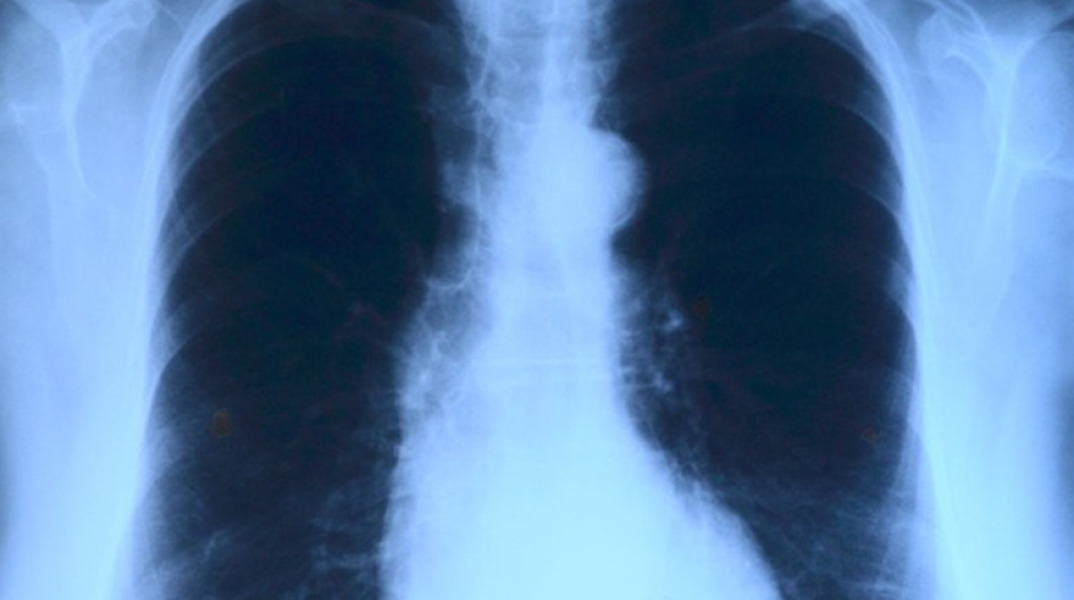

Σύστημα τεχνητής νοημοσύνης της Google σε ρόλο ακτινολόγου

Μπορεί να μελετήσει ακτινογραφίες πνευμόνων και να βγάλει αξιοπιστα συμπεράσματα

Ένα νέο σύστημα τεχνητής νοημοσύνης της Google ερμηνεύει τις ακτινογραφίες των πνευμόνων εξίσου καλά με έμπειρους ακτινολόγους.

Ένα νέο σύστημα τεχνητής νοημοσύνης της Google Health, θυγατρικής της Google στο πεδίο της «έξυπνης» υγείας, μπορεί να μελετήσει ακτινογραφίες πνευμόνων και να βγάλει συμπεράσματα εξίσου αξιόπιστα με εκείνα των έμπειρων ακτινολόγων. Το σύστημα βαθιάς μάθησης της Google, σύμφωνα με τους δημιουργούς του, μπορεί να αποτελέσει πολύτιμο βοηθό των γιατρών στο μέλλον.

Οι ερευνητές, που έκαναν τη σχετική δημοσίευση στο περιοδικό «Radiology» της Ακτινολογικής Εταιρείας της Βόρειας Αμερικής, εκπαίδευσαν το σύστημά τους τροφοδοτώντας το με περισσότερες από 860.000 ακτινογραφίες. Η ακτινογραφία πνευμόνων είναι από τις συχνότερες εξετάσεις παγκοσμίως, όμως έχει ορισμένους περιορισμούς.

«Βρήκαμε ότι υπεισέρχεται σε μεγάλο βαθμό ο υποκειμενικός παράγοντας στην ερμηνεία της συγκεκριμένης ακτινογραφίας, κάτι που περιορίζει την αποτελεσματικότητά της», ανέφερε ο επικεφαλής ερευνητής της Google Health, Σράβια Σέτι.

«Η ερμηνεία των ακτινογραφιών των πνευμόνων συχνά γίνεται με υποκειμενικό τρόπο, κάτι προβληματικό από την οπτική γωνία της βαθιάς μάθησης. Καταφέραμε να παράγουμε ένα σύστημα που κάνει πιο αξιόπιστη αξιολόγηση», δήλωσε ο συνάδελφός του, Ντάνιελ Τσε.

Οι δοκιμές του συστήματος από επιτροπή ακτινολόγων έδειξαν ότι τα καταφέρνει τουλάχιστον εξίσου καλά με τους γιατρούς στην ανίχνευση διαφόρων προβλημάτων (διάγνωση καταγμάτων, οζιδίων, όγκων, πνευμοθώρακα κ.ά.).